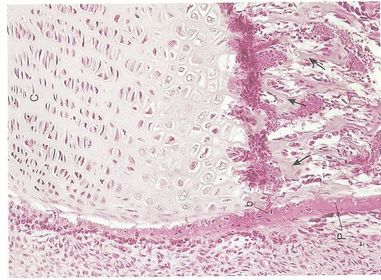

OSIFICACIÓN ENDOCONDRAL Se produce la formación de nuevo tejido óseo a partir de un molde en miniatura de cartílago hialino (vida intrauterina).

OSIFICACIÓN ENDOCONDRAL El cartílago se reabsorbe a medida que se forma el tejido óseo. Osificación= crear nuevo tejido óseo Osificación endocondral= a partir de un molde de cartílago

OSIFICACIÓN ENDOCONDRAL 4) ¿Cómo se observar la osificación endocondral desde el punto de vista histológico? 5) ¿Qué tinciones histológicas se utilizan para evidenciar la osificación en el tejido óseo?. 6) ¿Qué estructuras se identifican en la osificación con el microscopio de luz?.

OSIFICACIÓN ENDOCONDRAL Discusión con el profesor sobre el aprendizaje obtenido mediante la presentación de esquemas. Observar y analizar muestras de tejidos óseo con el microscopio de luz con la guía del profesor.